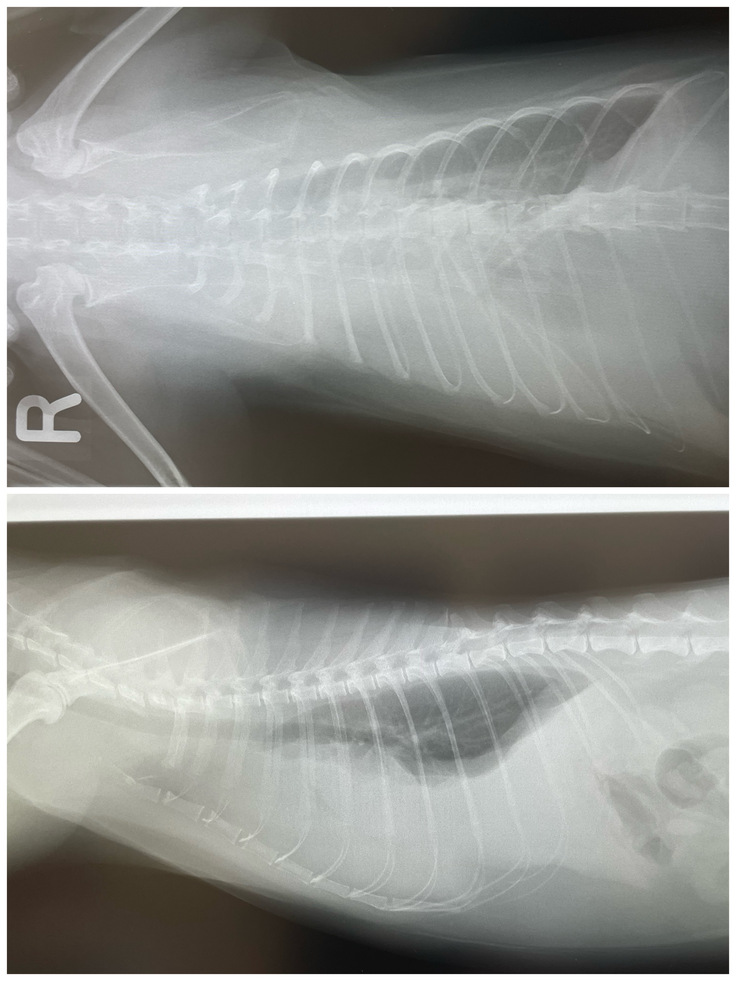

レントゲン検査では、心臓や肺が映らないほど胸水が溜まっていることが判明し、じじまるは、そのまま即入院となりました。

(正面図:右肺が全くうつらない)

(側面図:心臓も肺も全くうつらない)

(ドレーン手術後のレントゲン。胸水は膿水ということがわかり、生理食塩水で洗浄し薄めながら徐々に取り出すことに)

1週間程、ドレーンにて膿胸の洗浄排出を繰り返しようやく心臓と肺の影が見えてきました。

(ドレーンが肺上部に入っているのがわかる)

(正面図:右肺がやはりうっすらぼやけている)

(側面図:心臓は見え出したがまだぼやけている)